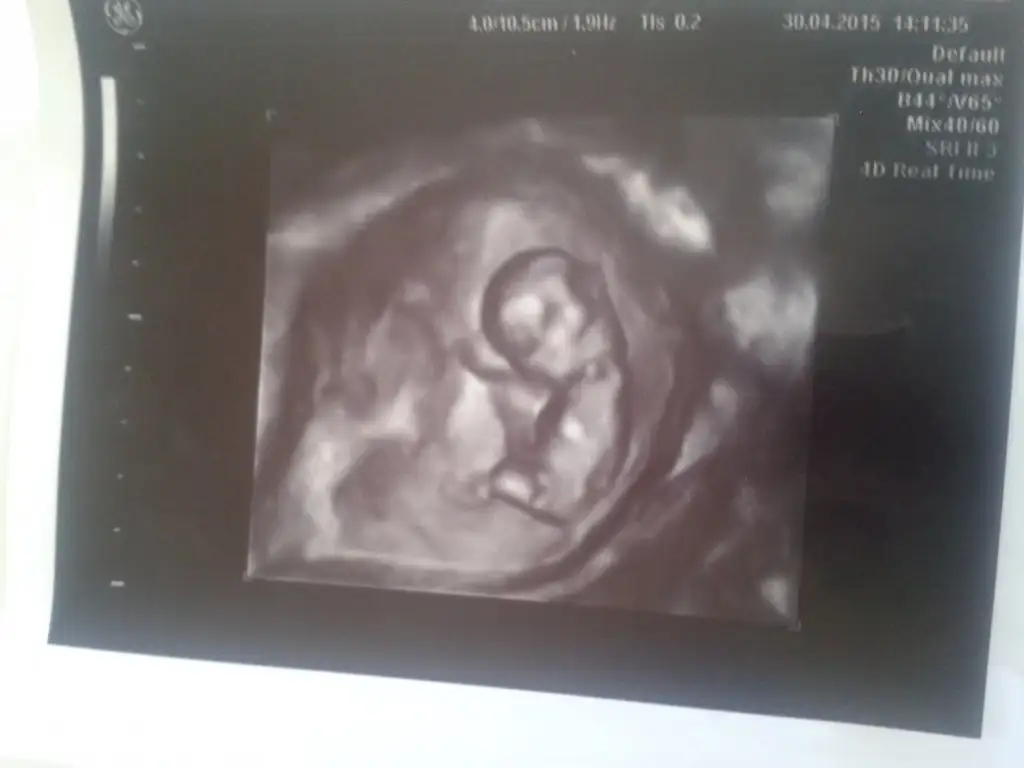

Hastaneden geldim son halimiz 18 haftalikmis bi bakın kizlarrrrr belki gorursunuz

• IMAG0093.webp

IMAG0093.webp

12,3 KB · Görüntüleme: 142

Genel olarak erkek diye tahminler yapildi ama kizmis bebegim.fikir olur size diye tekrar yukluyorun resmini